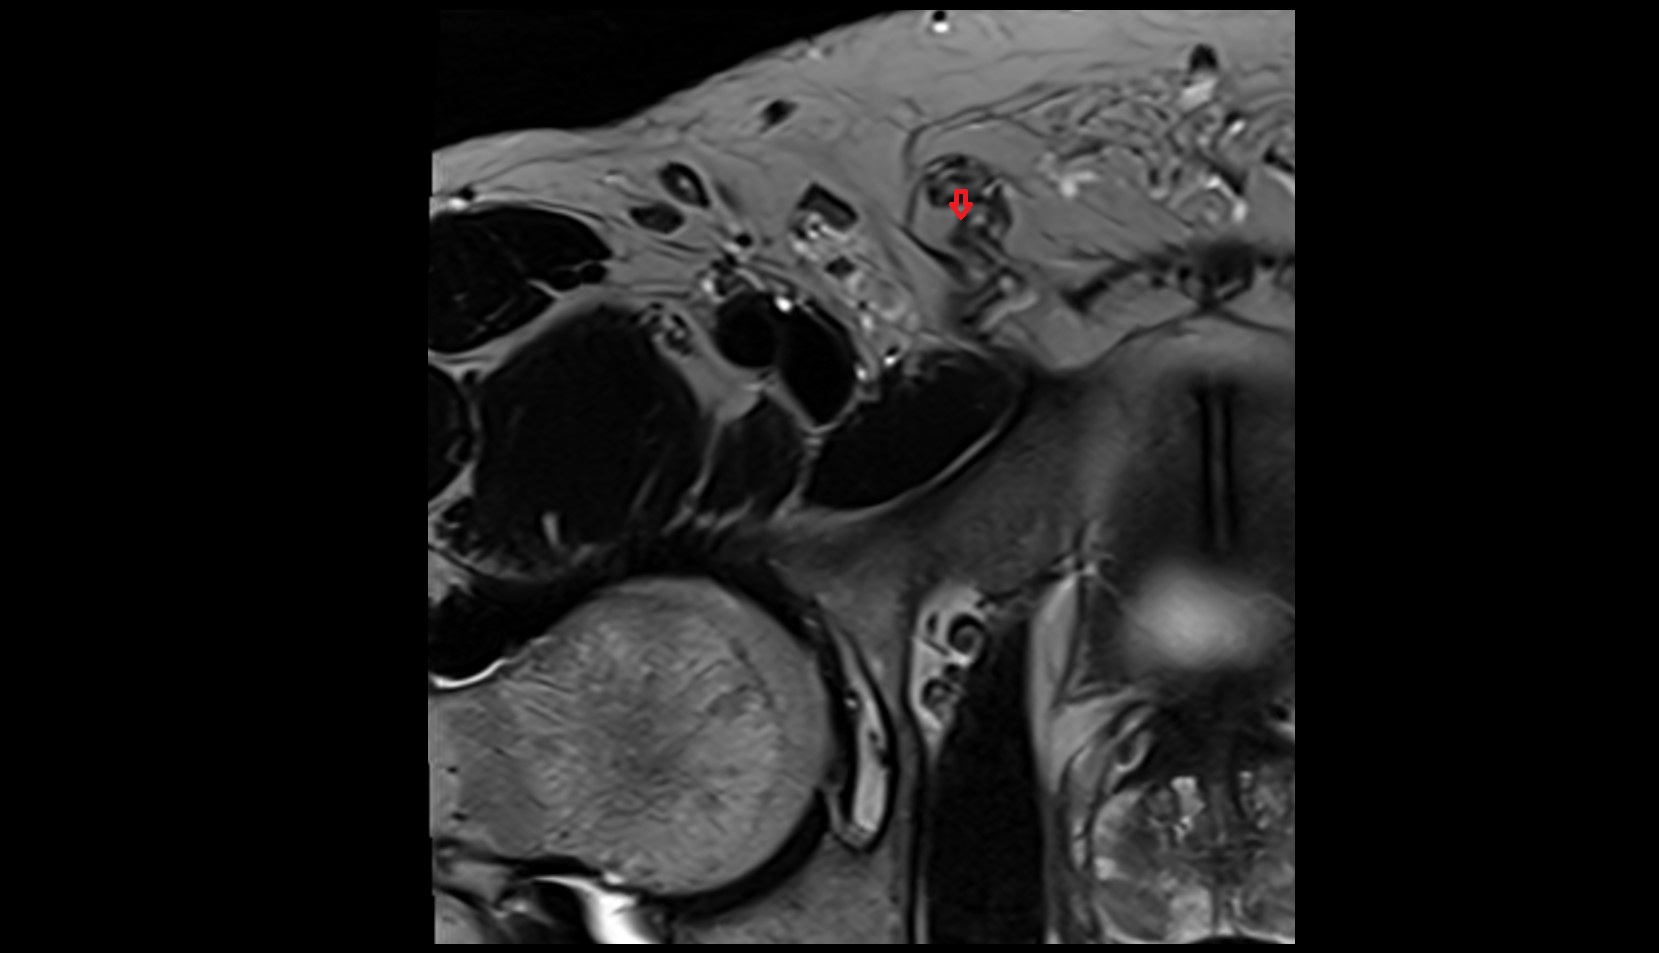

- Temporomandibular joint

- Mandibular condyle

- Mandibular fossa

- Articular disc of temporomandibular joint

- Articular eminence